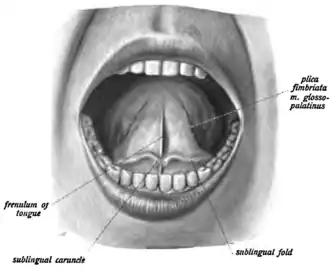

The submandibular duct (also Wharton's duct or historically submaxillary duct) is one of the salivary excretory ducts. It is about 5 cm long, and its wall is much thinner than that of the parotid duct. It drains saliva from each bilateral submandibular gland and sublingual gland to the sublingual caruncle in the floor of the mouth.

The submandibular duct arises from deep part of submandibular gland, a salivary gland. It begins by numerous branches from the superficial surface of the gland, and runs forward between the mylohyoid, hyoglossus, and genioglossus muscles. It then passes between the sublingual gland and the genioglossus and opens by a narrow opening on the summit of a small papilla (the "sublingual caruncle") at the side of the frenulum of the tongue. It lies superior to lingual and hypoglossal nerves.

The submandibular ducts drain saliva from the submandibular and sublingual glands to the sublingual caruncles in the floor of the mouth[3]